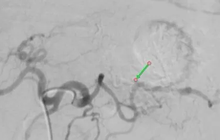

Kết quả MRI não phát hiện khối u vùng tuyến tùng - vị trí nằm sâu giữa não, dễ gây chèn ép đường lưu thông dịch não tủy, làm tăng áp lực nội sọ và gây đau đầu, nôn ói kéo dài. Nhận định tính chất nguy hiểm, cơ sở y tế địa phương đã chuyển em đến Bệnh viện Đa khoa Xuyên Á TP Hồ Chí Minh để tiếp tục điều trị.

Các bác sĩ Khoa Sọ não cột sống 2, Khoa Ung bướu và Khoa Xạ trị - Y học hạt nhân hội chẩn và thống nhất điều trị đa mô thức. Trước tiên, bệnh nhân được phẫu thuật đặt ống dẫn lưu não thất - ổ bụng (VP shunt) để giải quyết tình trạng ứ dịch não tủy, giúp giảm áp lực nội sọ. Sau phẫu thuật, triệu chứng đau đầu và chóng mặt cải thiện rõ rệt.

Theo ThS.BSCKI Nguyễn Hữu Huy - Trưởng Đơn vị Hóa trị, bệnh nhân được chẩn đoán mắc bướu mô đệm vùng tuyến tùng, nhóm u đáp ứng tốt với hóa trị. Vì vậy, bệnh nhân được hóa trị trước, sau đó đánh giá hiệu quả để lên kế hoạch phối hợp xạ trị đồng thời. Việc đánh giá sẽ dựa trên hình ảnh MRI và xét nghiệm máu theo dõi marker ung thư.